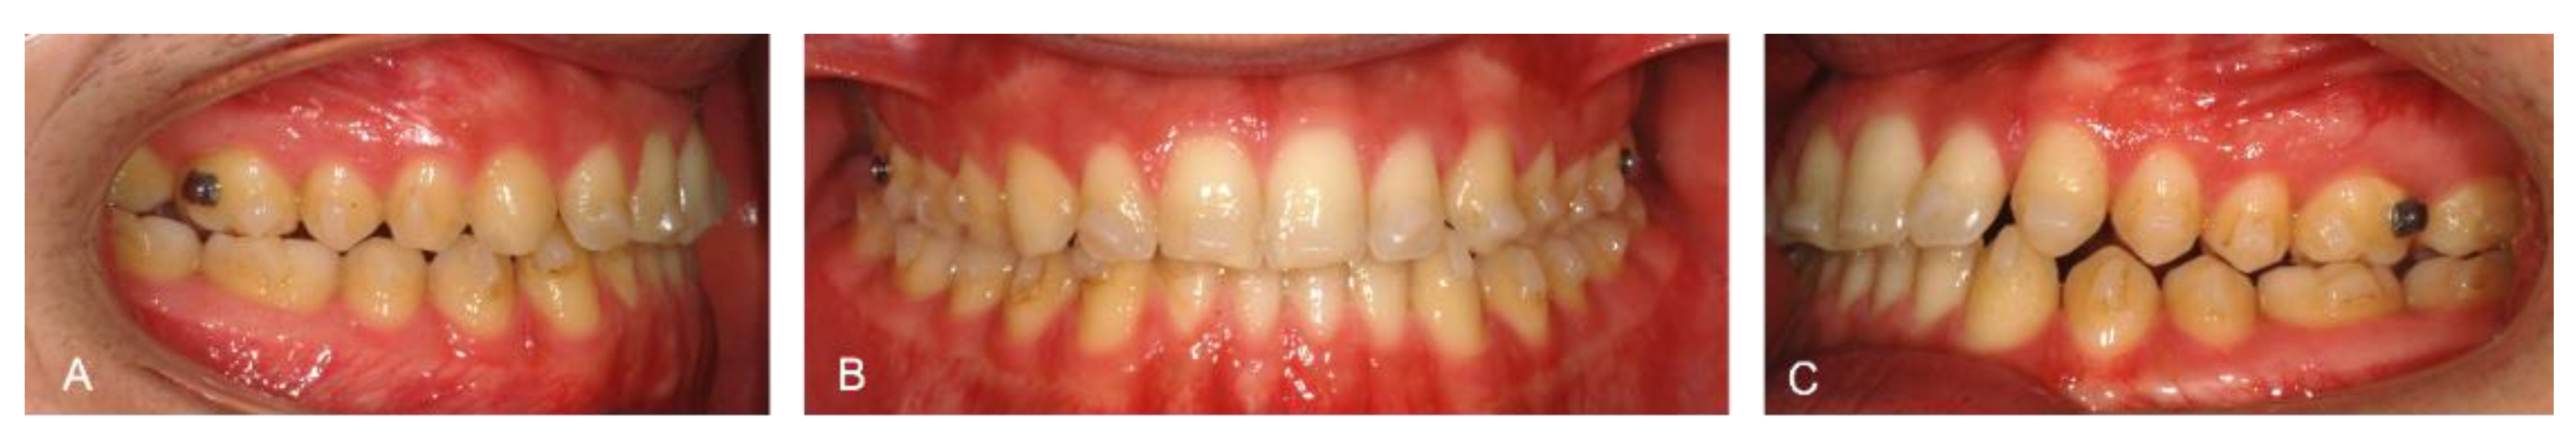

A 25-year-old patient had skeletal and dental class III malocclusion, anterior crossbite and incisal head-to-head relationship. This produced not only functional and aesthetic alterations but also occlusal trauma and incisor wearing. During childhood, the patient had already been orthodontically treated with multibrackets equipment and a palatal expander. Unfortunately, an orthodontic relapse occurred during adulthood, so the patient asked for re-treatment with a lower aesthetic impact and greater comfort than his previous experience (Figure 1).

Figure 1. Extra and intraoral photos of the patient before treatment: Right lateral occlusion (A); Frontal occlusion (B); Left lateral occlusion (C); Upper occlusion (D); Lower occlusion (E); Patient smile (F) and right profile (G).

Figure 5. Intra-oral pictures of the patient after the first treatment phase: Right lateral occlusion (A); Frontal occlusion (B); Left lateral occlusion (C).

Figure 6. Intra and extra-oral pictures of the patient at the end of treatment: Right lateral occlusion (A); Frontal occlusion (B); Left lateral occlusion (C); Upper arch (D); Lower arch (E); Patients smile (F) and profile (G).